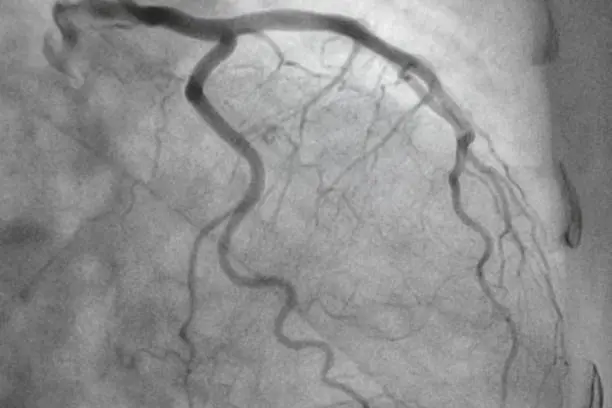

Contrast dye is injected, and X-ray images track the blood flow in real-time.

Findings are shared immediately. If a blockage is found, treatment like angioplasty may be done on the spot.